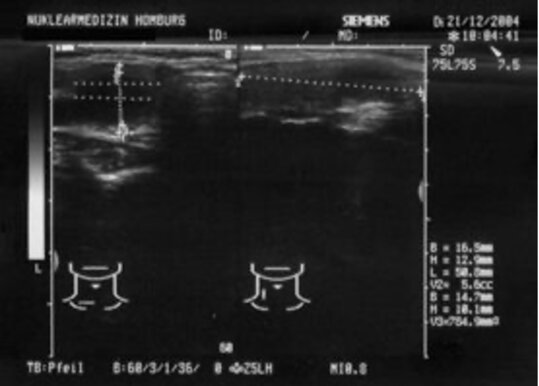

Eine bildgebende Untersuchung, die die Funktion der Schilddrüse darstellt und bei der Diagnose von Schilddrüsenknoten und -funktionsstörungen hilft. - Ultraschalluntersuchungen

Hochauflösende Ultraschalltechnik zur Beurteilung der Schilddrüsenstruktur und -größe. - Betreuung in der Schwangerschaft und bei Kinderwunsch

Um eine Struma zu diagnostizieren, muss eine genaue Bestimmung von Größe, Lage und Struktur der Schilddrüse durch eine klinische Untersuchung und durch Ultraschall erfolgen. Ist die Schilddrüse gleichmäßig vergrößert, spricht man von einer diffusen Struma. Falls sich Knoten innerhalb der Schilddrüse gebildet haben, besteht eine Knotenstruma.